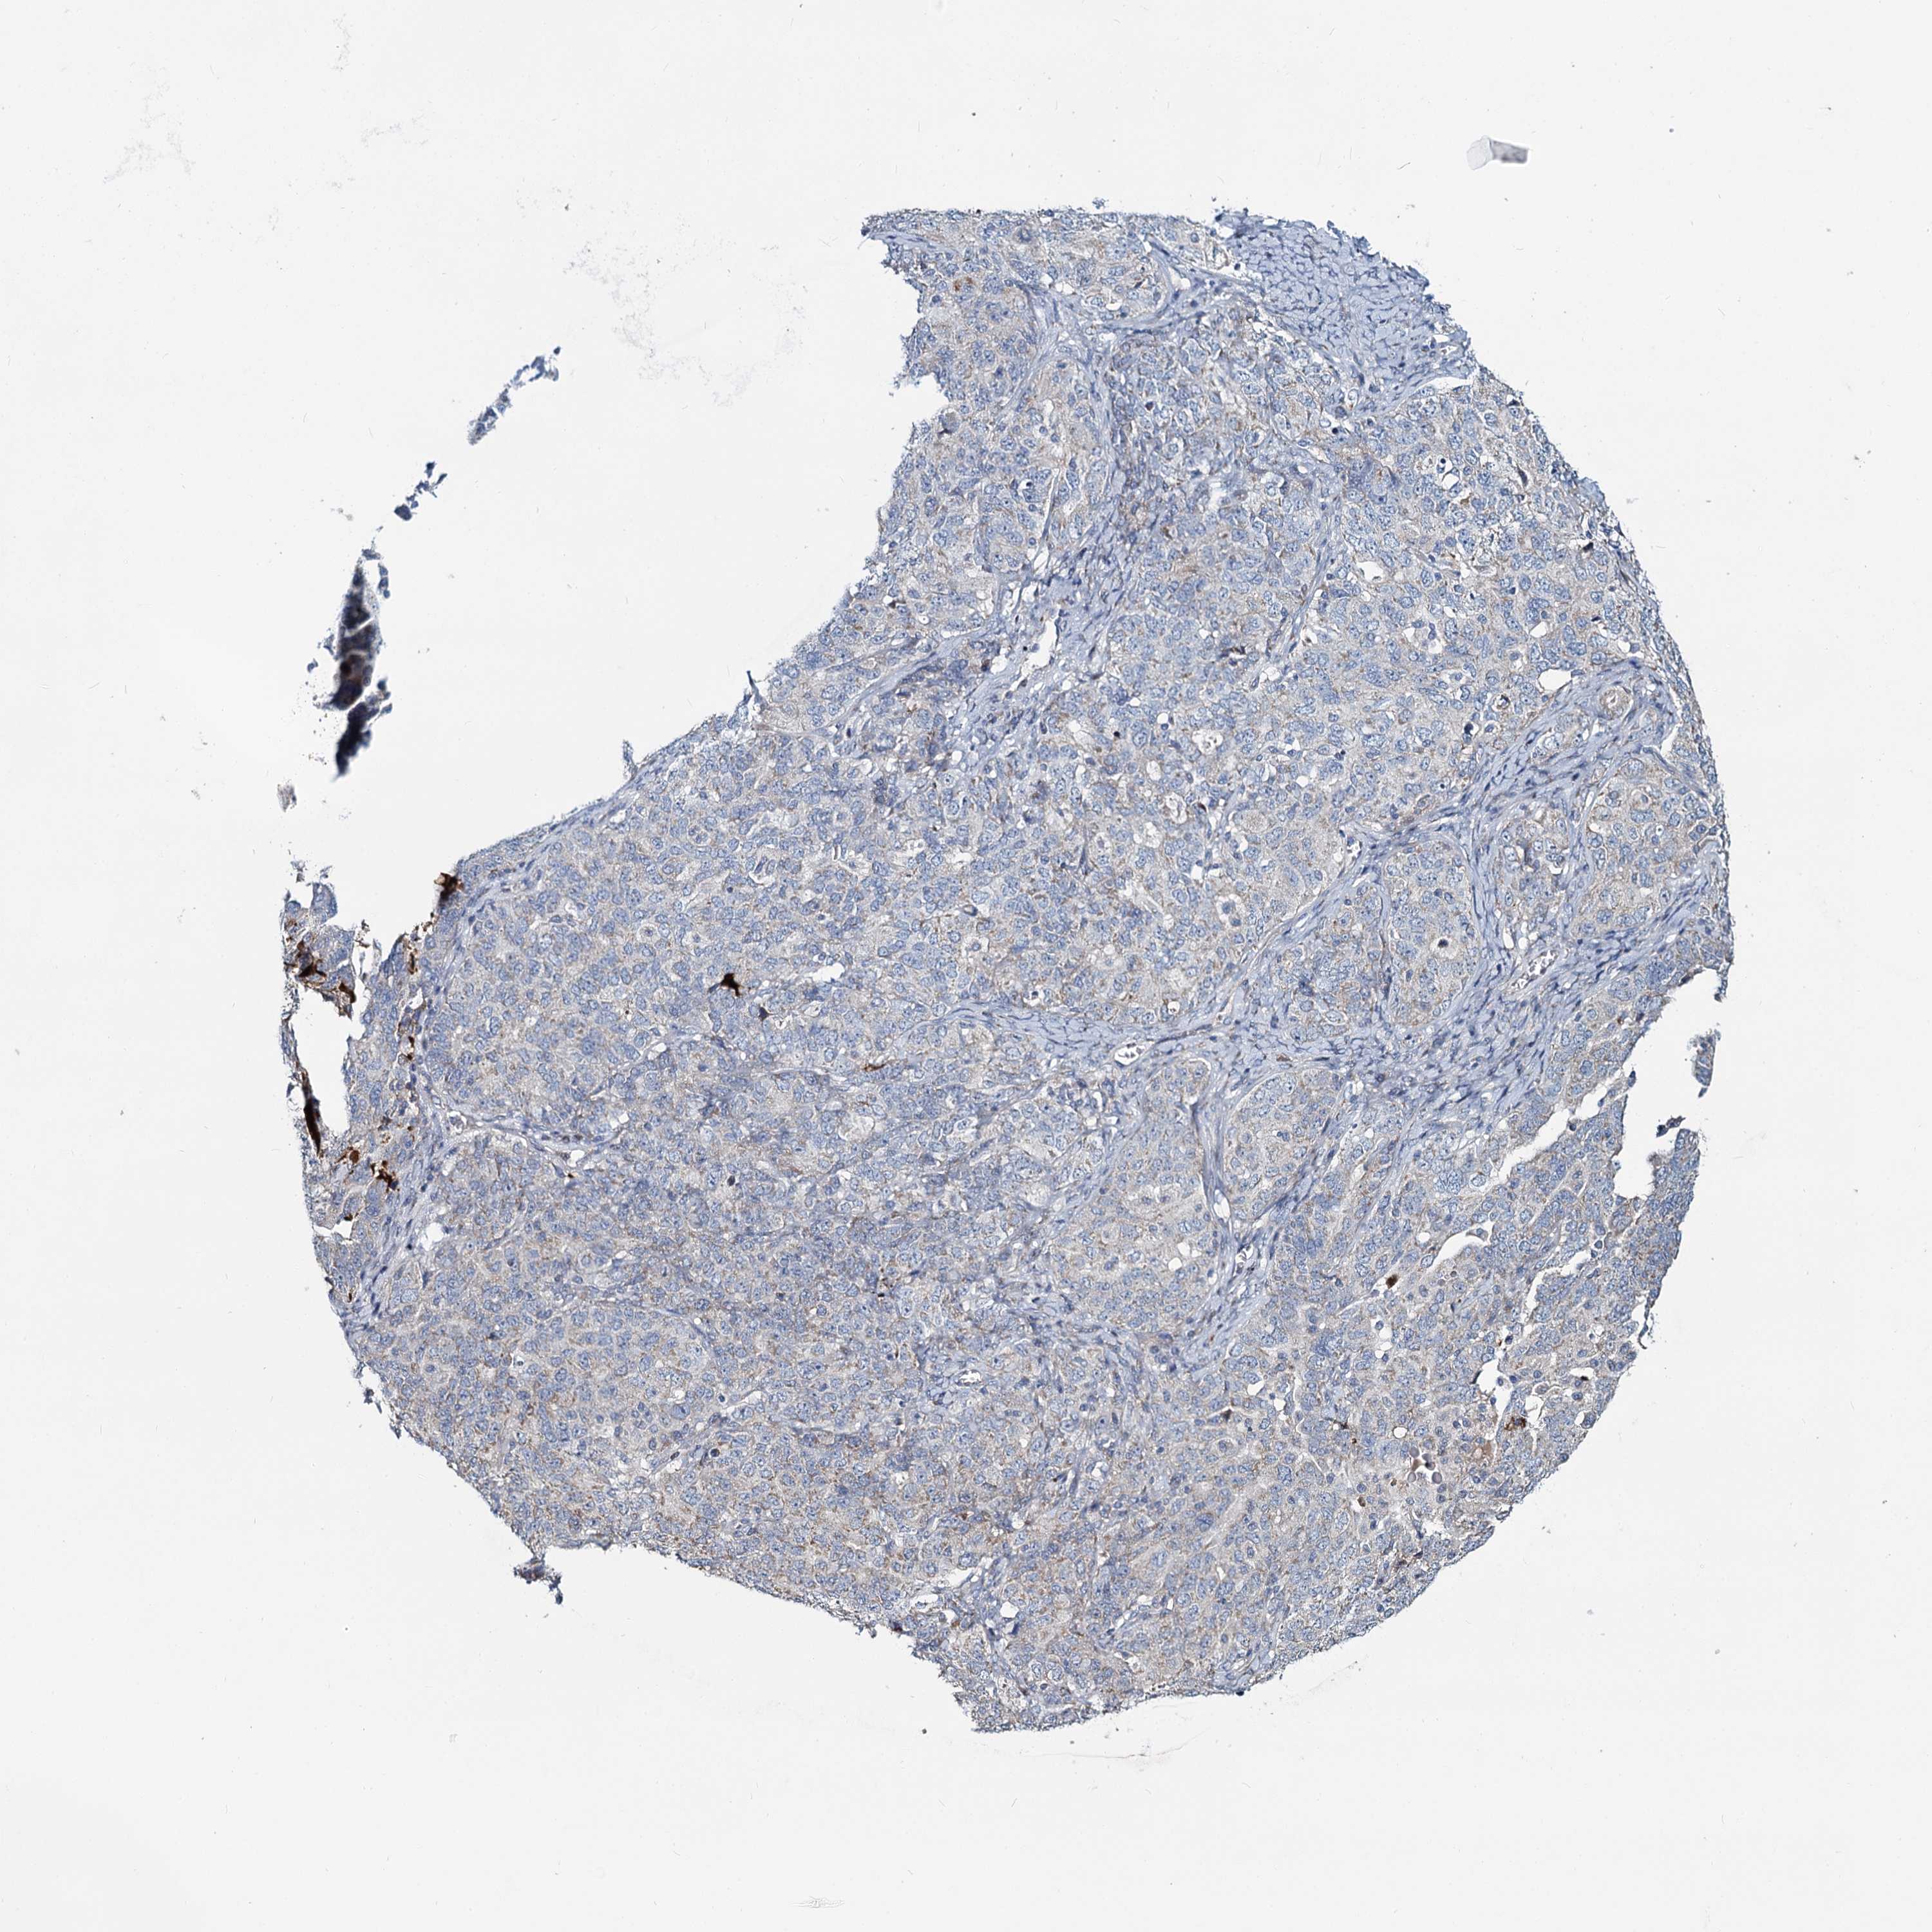

OVARIAN CANCER - Protein expressioni

A mouse-over function shows sample information and annotation data. Click on an image to view it in a full screen mode. Samples can be filtered based on level of antibody staining by selecting one or several of the following categories: high, medium, low and not detected. The assay and annotation is described here.

Note that samples used for immunohistochemistry by the Human Protein Atlas do not correspond to samples in the TCGA dataset.

Antibody stainingi

Antibody staining in the annotated cell types in the current human tissue is reported as not detected, low, medium, or high, based on conventional immunohistochemistry profiling in selected tissues. This score is based on the combination of the staining intensity and fraction of stained cells.

Each image is clickable and will lead to virtual microscopy that enables deeper exploration of all samples and also displays staining intensity scores, fraction scores and subcellular localization as well as patient and tissue information for each sample.

Antibody HPA039349

Staining

High

Medium

Low

Not detected

Intensity

Strong

Moderate

Weak

Negative

Quantity

>75%

75%-25%

<25%

None

Location

Nuclear

Cytoplasmic/membranous

Cytoplasmic/membranous,nuclear

Cystadenocarcinoma, serous, NOS

Carcinoma, endometroid

Cystadenocarcinoma, mucinous, NOS

Carcinoma, NOS